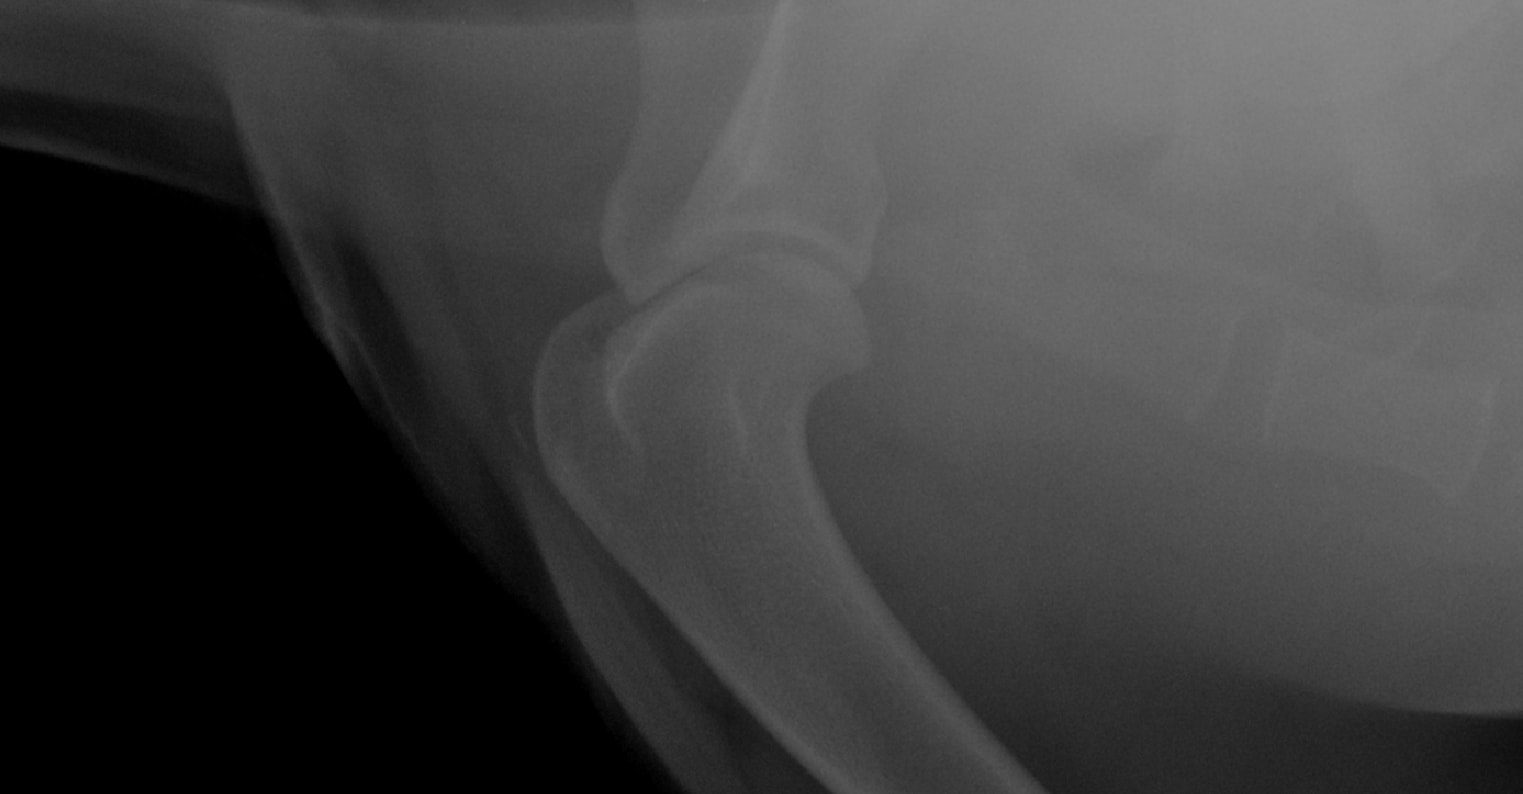

Hi Again, I asked a question recently regarding my rottie - We had a 2nd opinion at a specialist. they also cannot tell us what is wrong. They took xrays again and said it is inflamed. so they put him again on anti inflams - they said he has to go back in a month because they suspect bone cancer - I don't understand why they cannot test for it. they suspect bone cancer in his shoulder. its either that or his cartlidge is damaged. I don't want to wait 4 weeks and do nothing. please help.

The bone lesion is small on the xray. Diagnosing bone cancer can sometimes be difficult on the smaller lesions. A bone biopsy is something they might consider. Your specialist is likely waiting to see if the changes become more pronounced in order to obtain a better sample. A CT scan should be considered as well. This breed is predisposed to certain cancers and we see bone cancer commonly in this breed. Please let me know if you have any other questions or concerns.